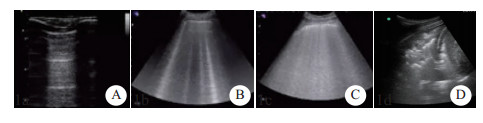

1.2.1 床旁肺部超声检查①患者仰卧位选择凸阵探头(Sonosite M-Turbo 2-5 MHz),探头垂直于肋间隙,根据中国重症超声专家共识推荐的检查方法[7],分别于双侧胸壁的上蓝点、下蓝点、PLAPS点、后背检查B线数目。每个检查点观察采集切面下吸气相最多的B线数目并进行计数,1条B线计1分,出现肺部实变征象(即碎片征)记5分,然后计算总和,即为肺部超声B线积分(LUBS),并统计双侧肺超LUBS数值。见表 1。

| A:图片表现为A线,记0分;B:图片表现为散在的B线,图中可见4条B线,每条B线计1分,共4分;C:图片表现弥漫性B线,最多可见7条B线,共计7分;D:图片出现实变征,共计5分 图 1 超声B线计分及常见超声图像模式 |